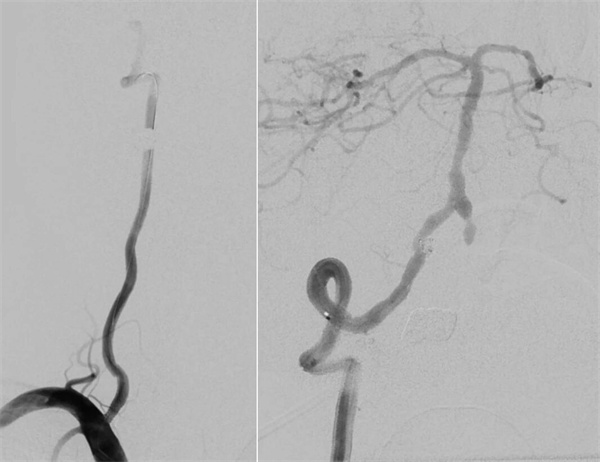

▲右侧颈内动脉颅外段重度狭窄,左侧颈内动脉代偿右侧颅内

第四步,最终验证。再次造影显示:狭窄消失,支架位置良好。动脉瘤不显影,弹簧圈致密填塞。

手术历时约2.5小时,患者术后头部昏沉感明显好转,次日顺利出院,无新发神经功能障碍。